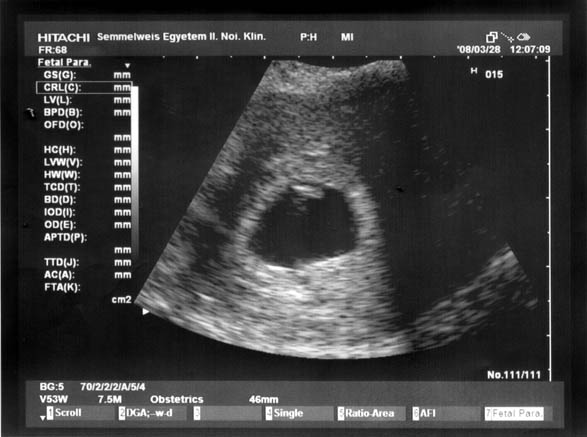

Tegnapelőtt megvolt a vizsgálat, uhz, minden. És szerencsére minden oké, CRL 10 mm, és jó erős szívhangja volt! Nagyon jó érzés volt, páromat is behívták! Még így harmadszora is nagyon meg tudott hatni! Mutizom a képet:

Kép